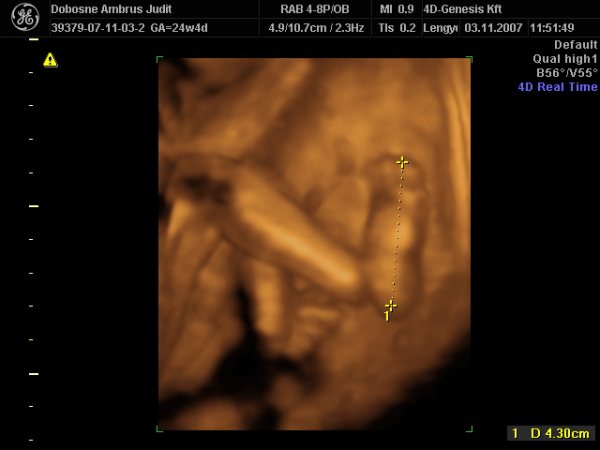

31 hetes